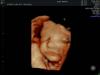

На каком сроке лучше делать 3д УЗИ?

27-29 недель идеальный срок. У меня в 30 недель сын уже перевернулся головой вниз, а там уже неудобно 3д делать.

Согласна , делала в 26 и человека можно разглядеть

26-30 мне говорили в клинике. Я делала в 27 в обе беременности, идеально, хорошо получилось

Лучше на 28-30, мне на 24 смотрели в 3д лицо еще такое худенькое было, а в 28 уже такая лялька щекастенькая

Сделала на 24 лицо кое как, но поймали

Планирую к 28 еще разок попробовать)))

25-30

после 30 мне врач сказала уже сложно поймать картинку красивую, малышу места уже мало и вод много

но тут все индивидуально, некоторые и в 33 ходят и получают красивые кадры

мы в 25 ходили, идеально все рассмотрели

Средний срок смотрю 24-28 недель по клиникам Москвы